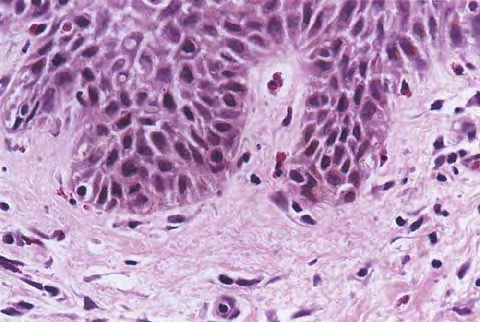

Read MoreUrticarial bullous pemphigoid = الفقاعاني الفقاعي الشروي Bullous Pemphigoid First described in 1953 by Lever, bullous pemphigoid affects primarily elderly patients with large tense bullae arising on urticarial erythematous bases or on nonerythematous skin .In contrast to pemphigus, the Nikolsky sign is negative. The lesions involve the trunk, the extremities, and the intertriginous areas, with […]